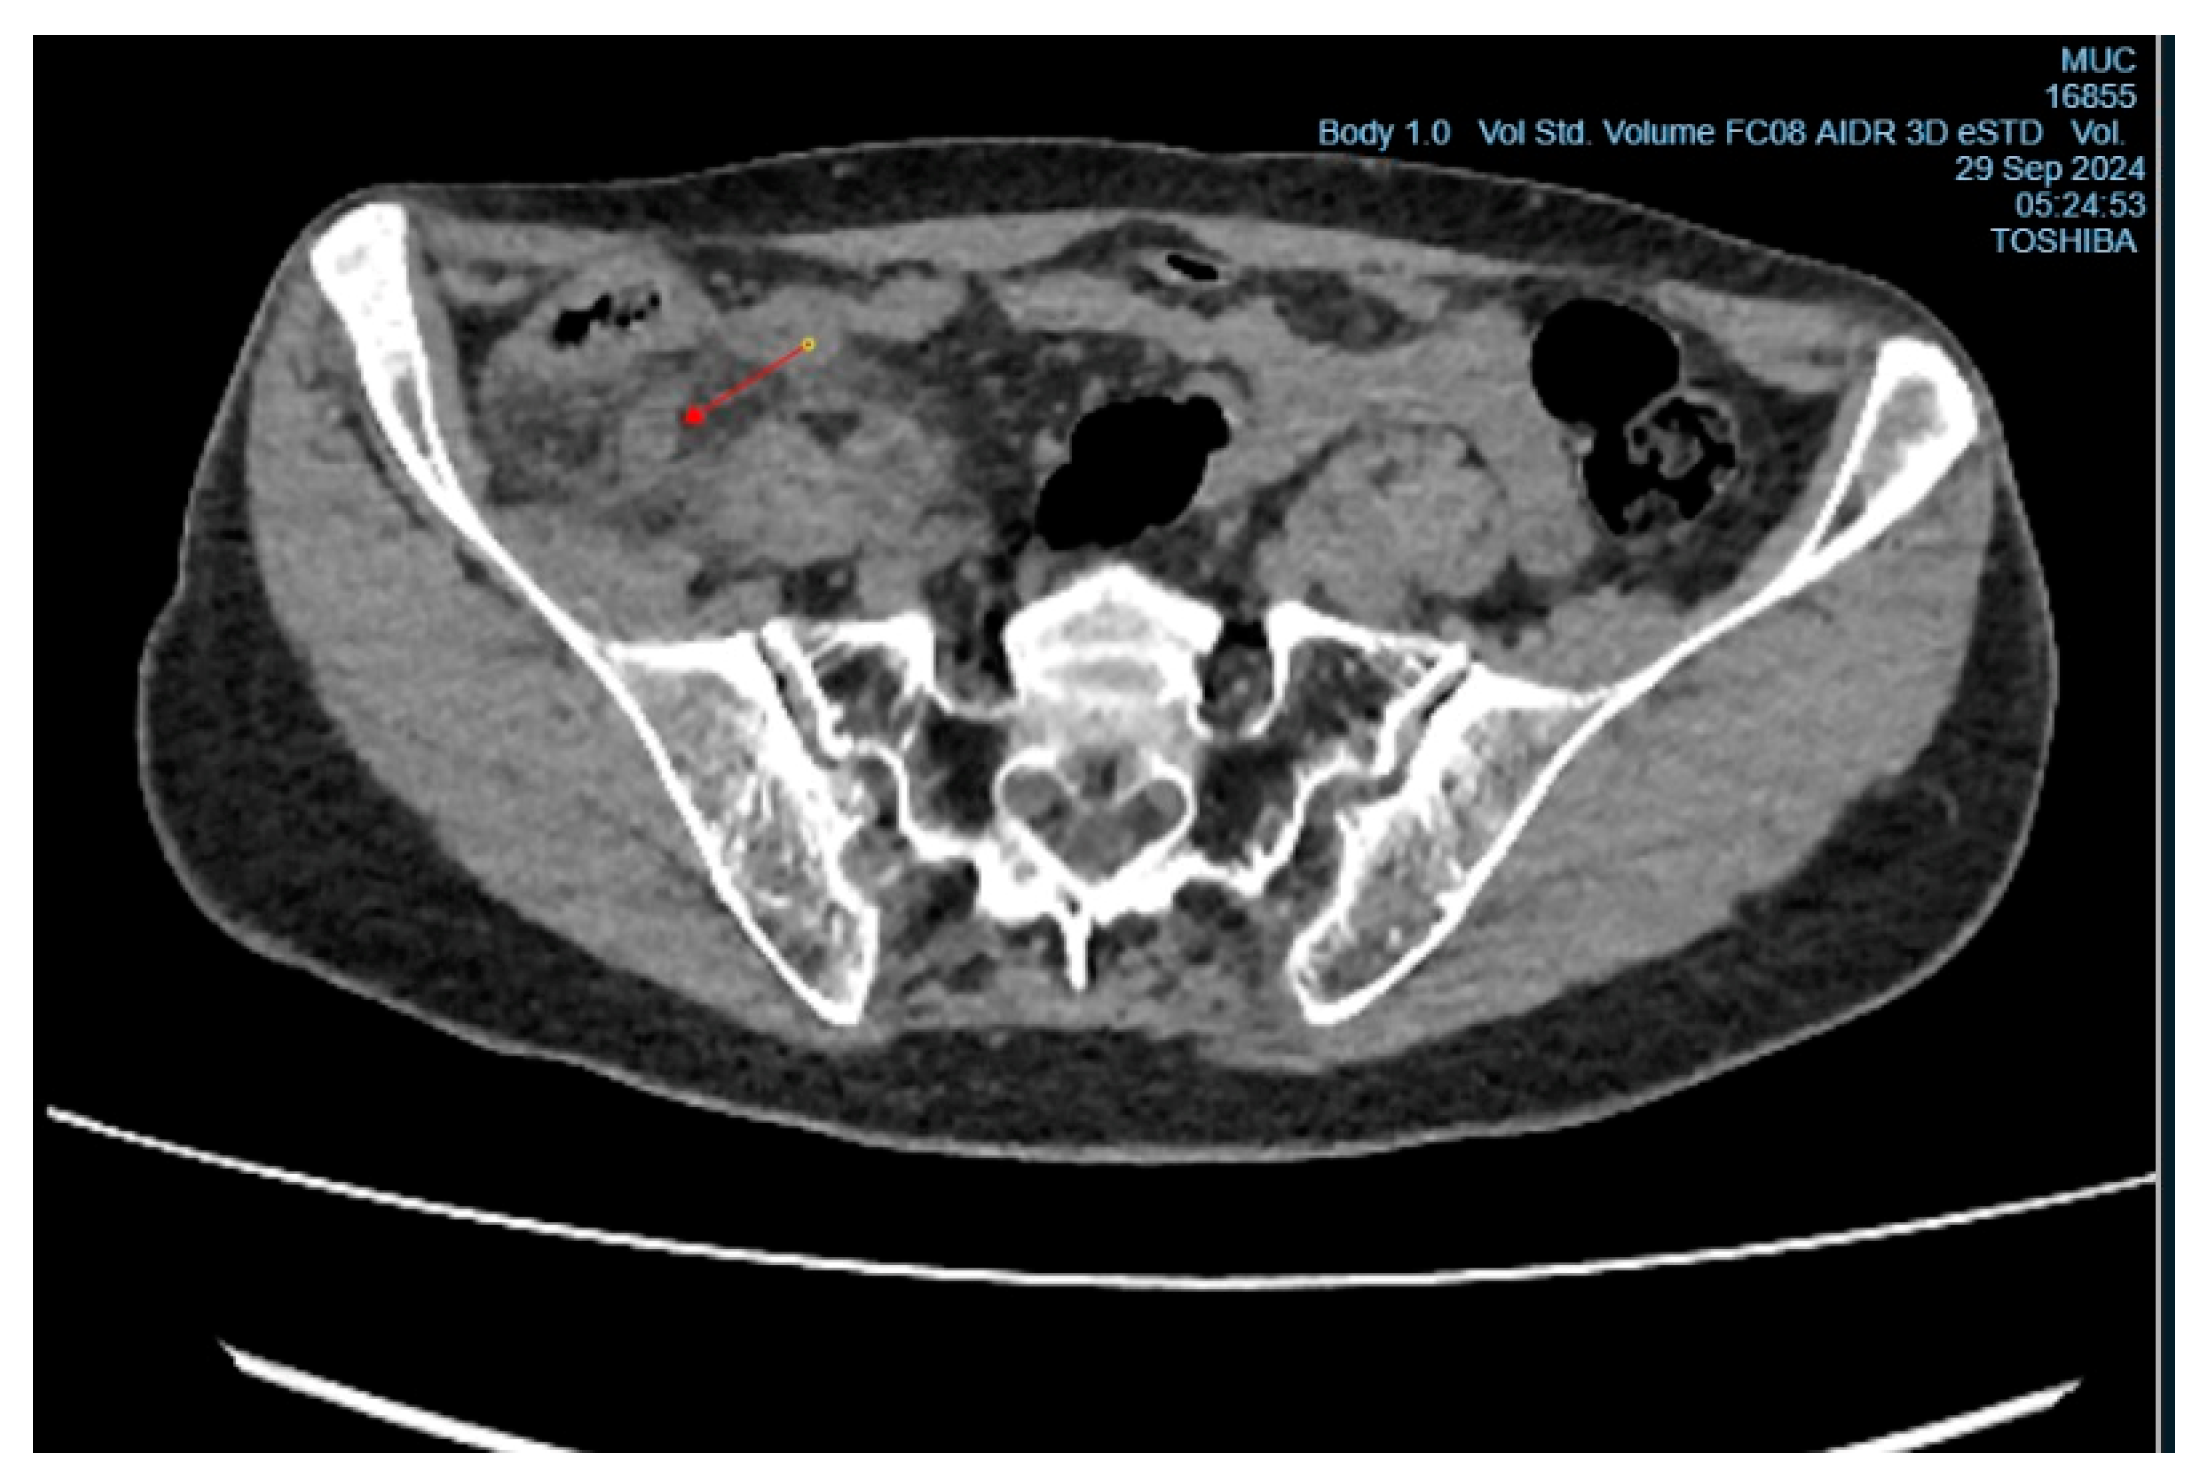

Upon examination, the patient showed tenderness on palpation in the right iliac region, with positive signs of Sitkovsky, Rovsing, and Bartomé-Michelson. Laboratory tests revealed an elevated level of C-reactive protein (6 mg/L, reference range <5 mg/L), while the white blood cell count was within normal limits. A computed tomography (CT) scan of the abdominal organs showed signs of acute appendicitis (Figure 1 and Figure 2). The patient underwent surgery – an open appendectomy through an oblique incision according to Volkovich-Dyakonov. Intraoperatively, the diagnosis of acute phlegmonous appendicitis was confirmed.

Figure 1. CT image of acute appendicitis, presented in the frontal projection.